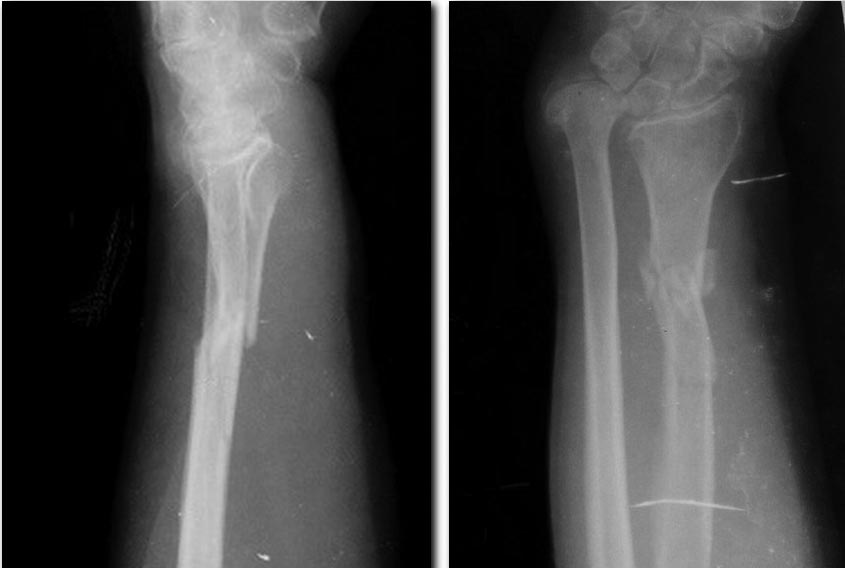

Добрый день, подскажите пожалуйста с тактикой лечения. Женщина 55лет, 15 лет назад получила травму правого предплечья: скорее всего перелом правой лучевой кости с разрывом дистального радиоульнарного сочленения (?), за медицинской помощью не обращалась, вследствие чегоразвилось укорочение правой лучевой кости, возникла правосторонняя косорукость. 4.09.2017г. упала на правое предплечье, обратилась за медицинской помощью, на рентгенограмме:оскольчатый перелом правой лучевой кости с смещение осколков. Предполагаемая тактика лечения: 1.фиксация перелома лучевой кости аппаратом внешней фиксации с постепенной дистракцией отломков(1мм в сутки) закрыто, либо если дистракция закрыто не получится - открытая репозиция, остеотомия лучевой кости в области консолидирующего перелома, релиз рубцов дистальногорадиоульнарного сочленения.

2. Открытая репозиция перелома лучевой кости, ликвидация укорочения лучевой кости (получится лиодномоментно?) + возможная костная пластика, МОС пластиной, фиксация радиоульнарного сочленения кортикальным винтом. Извините за плохое качество рентген снимков(пациент не местный). Спасибо

Рентгенограммы

Андрей! К вам больная обратилась по поводу перелома лучевой кости. Вы не сравнивайте эту травму со свежим повреждением Галеацци. Остеосинтез пластиной лучевой кости. С дистальным суставом сложнее. Что больную не устраивало 15 лет, что беспокоило: боли, слабость в кисти, снижение силы хвата? Удлинение лучевой проигрывает перед укорочением локтевой. Тыльное смещение суставной луча больше допустимого. Диссоциация DRUJ, повреждение TFCC. Вопросов много и решить их нужно до операции. С уважением.

Добрый вечер, Антон. Спасибо за совет, согласен с Вами полностью. На данный момент больную беспокоит косорукость, ограничение движений в лучезапястном суставе, боль в области передплечья в области свежего перелома. Просто думал, что простой остеоситез лучевой кости не сможет решить её все(15 летней давности) проблемы. Почему она вовремя не обратилась 15 лет назад за помощью остается загадкой. Спасибо

Срастите свежий перелом луча, а потом удаляйте головку локтевой кости с тенодезом. За 15 лет от дистального радиоульнарного сочленения уже ничего не осталось и делать там нечего, тем более фиксировать винтом. Мне так кажется.

selectively. It may be useful in low-demand patients with severe DRUJ incongruity, arthritis, or ulnar impaction syndrome when an ulnar-shortening osteotomy or hemiresection arthro-plasty is unlikely to be successful." И еще. Не надо "наклонять" в ульнарную сторону суставную поверхность луча, чтобы после резекции головки не было ульнарной транслокации запястья. Сейчас на снимке вроде бы суставная поверхность стоит довольно прилично для операции Дарраха.